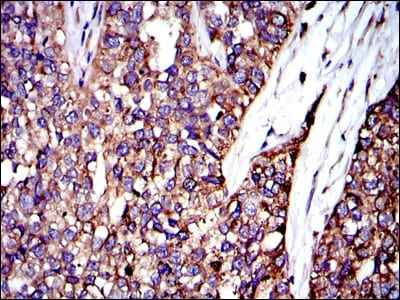

Immunohistochemical analysis of paraffin-embedded human rectum cancer tissues using CRK mouse mAb with DAB staining.

Immunohistochemical analysis of paraffin-embedded human bladder cancer tissues using CRK mouse mAb with DAB staining.